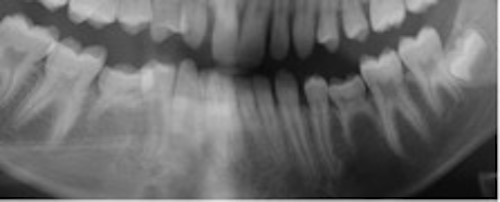

Infraocklusion av tänder innebär att tänderna befinner sig under ocklusalplanet hos angränsande tänder. Avståndet kan variera från någon millimeter till att ocklusalytan är under gingivakanten eller inte ens syns i munnen (1-4). I de flesta fall erupterar alla primära molarer upp till ocklusal kontakt med motstående tänder. Senare börjar en del hamna i infraocklusion och ibland blir de även ankylotiska.

I sällsynta fall kan primära molarer ses i infraocklusion redan i 3-4 årsåldern, men mest frekvent är infraocklusion i 9-10 års ålder (2). Omkring 14 % av barnen i dessa åldrar har en eller flera primära molarer i infraocklusion. Det förekommer dubbelt så ofta i underkäken som i överkäken. Infraocklusion av primära molarer förekommer ofta hos barn som även har andra tand- eller eruptionsavvikelser så som agenesi av premolarer, små eller tappformade överkäkslateraler, ektopisk eruption av överkäkens första permanenta molarer och retinerade överkäkshörntänder (5-8).